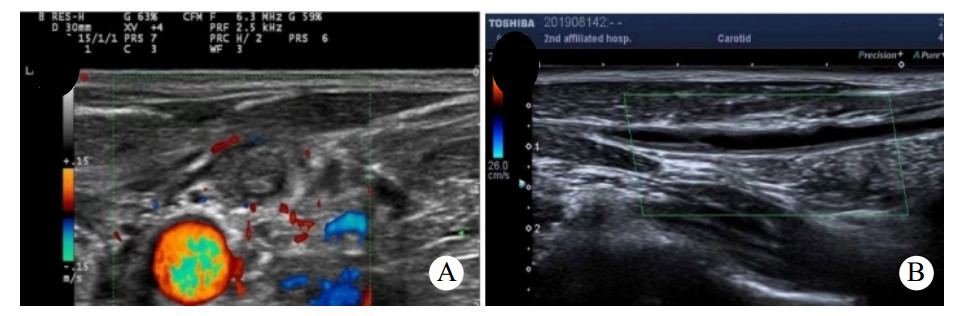

患者男,50岁,因“进行性左侧咽痛6 d”于2019年4月30日入院。患者6 d出现左侧牙痛、咽痛,伴发热(体温不详),未予治疗。3 d前咽痛加重,遂至当地医院就诊,CT提示左侧咽旁软组织肿胀伴喉腔变窄,超声提示左侧颌下腺炎,予以头孢米诺钠抗感染治疗后咽痛无好转,并出现呼吸困难及胸闷,左侧颈部肿痛。10 h前转入本院急诊就诊。否认糖尿病、高血压、吸烟、饮酒史。查体:双侧扁桃体无肿大充血,左侧咽侧壁肿胀,左侧颌下及颈部肿胀,压痛明显,局部皮肤红肿,皮温升高。血常规:白细胞计数7.2×109/L、中性粒细胞6.14×109/L、中性粒细胞百分比85.2%。C反应蛋白 > 270.0 mg/L。凝血谱:D-二聚体2960 μg/L、血浆纤维蛋白原10.98 g/L。颈胸部增强CT:左侧咽旁间隙、左侧颈部、中后纵膈脓肿形成,左侧颈内静脉血栓形成考虑,双侧胸腔积液。见图 1。拟诊为咽旁脓肿,纵膈脓肿,左侧颈内静脉血栓,胸腔积液。急诊行颈侧切开咽旁、颈部脓肿切排引流,纵膈胸膜切开排脓、胸腔脓肿清除、胸腔闭式引流。颈部留置引流管2根,食管后间隙留置胸管1根,右侧胸腔留置胸腔引流管1根。脓液送细菌培养和药敏检查。患者带气管插管入住ICU,予注射用亚胺培南西司他丁钠(泰能)0.5 g每6 h一次抗感染,那屈肝素钙注射液(速碧林)0.4 mL每12 h一次抗凝治疗,注射用甲泼尼龙琥珀酸钠(甲泼尼龙)40 mg每日3次抗炎,以及化痰、护胃、补液等对症支持治疗。术后第2天转入普通病房,细菌培养及药敏结果:咽峡炎链球菌,对当前使用抗生素敏感,未更改抗生素。术后2次血培养结果均为阴性。术后持续牙痛并有持续性低热,请口腔外科会诊,考虑牙源性感染,建议待感染控制后拔除病灶牙。术后白细胞总数逐渐增加,C反应蛋白及降钙素原逐渐下降。术后第9天,出现左侧颌下及颈部肿胀,压痛明显,局部皮肤红肿,皮温升高,急诊行颈部及胸部CT提示:咽旁、颈部、纵膈脓肿术后改变,左侧颈部软组织内及上纵隔积气。两肺背侧少许渗出,两侧少量胸腔积液伴部分肺组织膨胀不全,较前5月1日渗出有吸收,积液有增多,右侧叶间包裹性积液。考虑颈部引流不畅,急诊行颈侧切开颌下、咽旁、颈部脓肿切排引流,颈部重新放置2根引流管。术后白细胞总数开始下降。术后22 d出院,复查颈静脉超声(图 2A)提示左侧颈内静脉闭塞,出院后改用利伐沙班片20 mg口服每日3次,抗凝治疗3个月。术后4个月复查超声(图 2B),左侧颈内静脉部分再通。

| A:▲为颈部增强CT提示左侧咽旁间隙脓肿形成,△为左侧颈内颈内血栓形成;B:胸部增强CT提示纵隔脓肿,双侧胸腔积液 图 1 入院时的颈胸部增强CT |